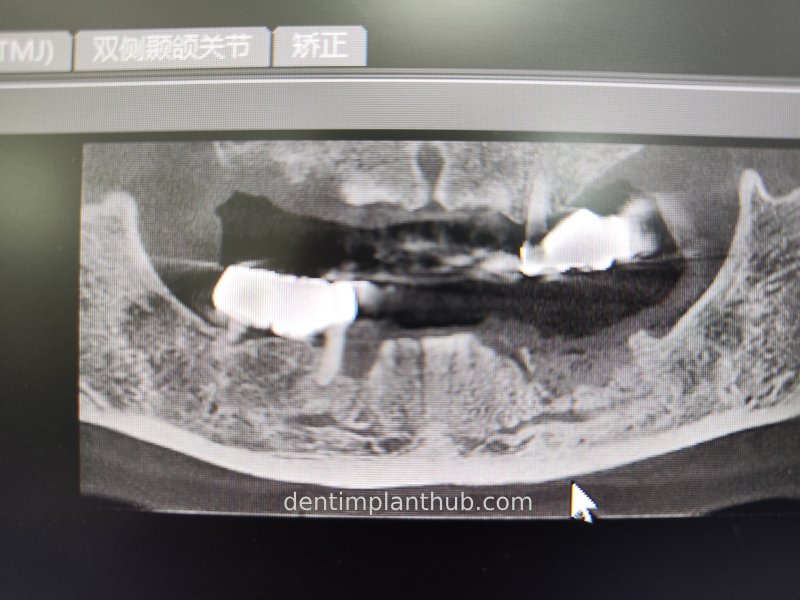

CBCT review results on 13 May '24

46

44

42

32

34

36

Maxillary condition as shown by CBCT on 13/5/24

16

14

12

22

24

26